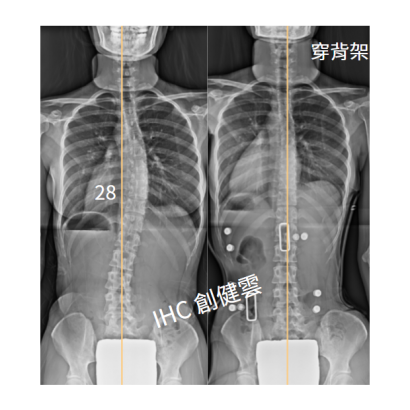

21歲成年女生,側彎28度

21歲脊椎側彎女生 胸彎28度

聲明: 以上背架矯正案例皆為創健雲團隊親自製作,未經同意請勿任意轉載及使用。任何背架矯治效果因人而異,必須由專家當面諮詢與評估。